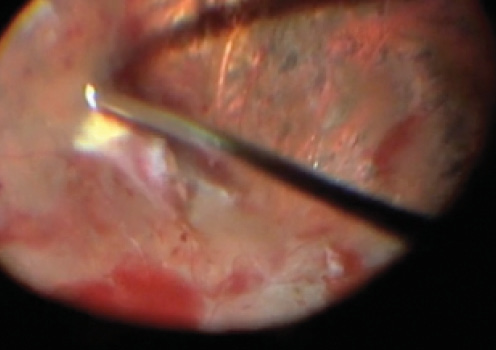

Figure 2. Shaving tissue over vessels using a 27-gauge vitrector.

The vitrector is used in aspiration mode to grasp an edge of membrane or hyaloid and to lift and peel as soon as resistance is encountered (Figure 1). The footpedal is then shifted to cutting mode, and the lifted tissue is removed. This maneuver is sequentially repeated, together with blunt dissection, until only tissue over the optic nerve and around vessels remains. Tissue over vessels can be shaved in cutting mode with minimal aspiration (Figure 2). Tissue over the optic nerve can be peeled using suction with the vitrector at maximum aspiration.